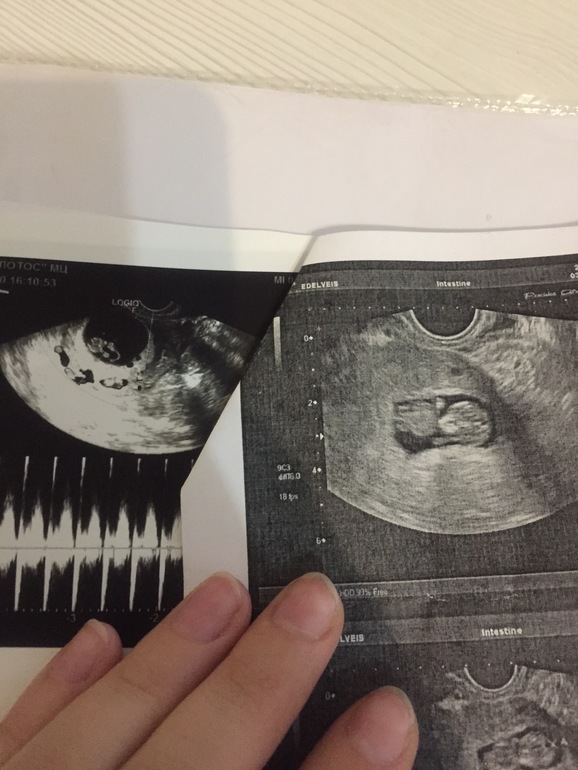

УЗИ 8-9нед

Девочки что то я не понимаю почему плохо видно карапуза?((( или по узи все нормально ?

Нормальный. На маленькую машинку похож. У меня такой же был) зависит де от аппарата и рук узиста)

Вы ещё мое узи в 9 недель не видели 😂Пупс крутится-вертится уже,фиг поймаешь)

На пустом месте проблему придумали 🤦🏼♀️ «Плохо видно»? Ну это же узи! Это не фотография. Он есть там, живой, сердце стучит, нет надо до чего-то докопаться) вам нельзя нервничать